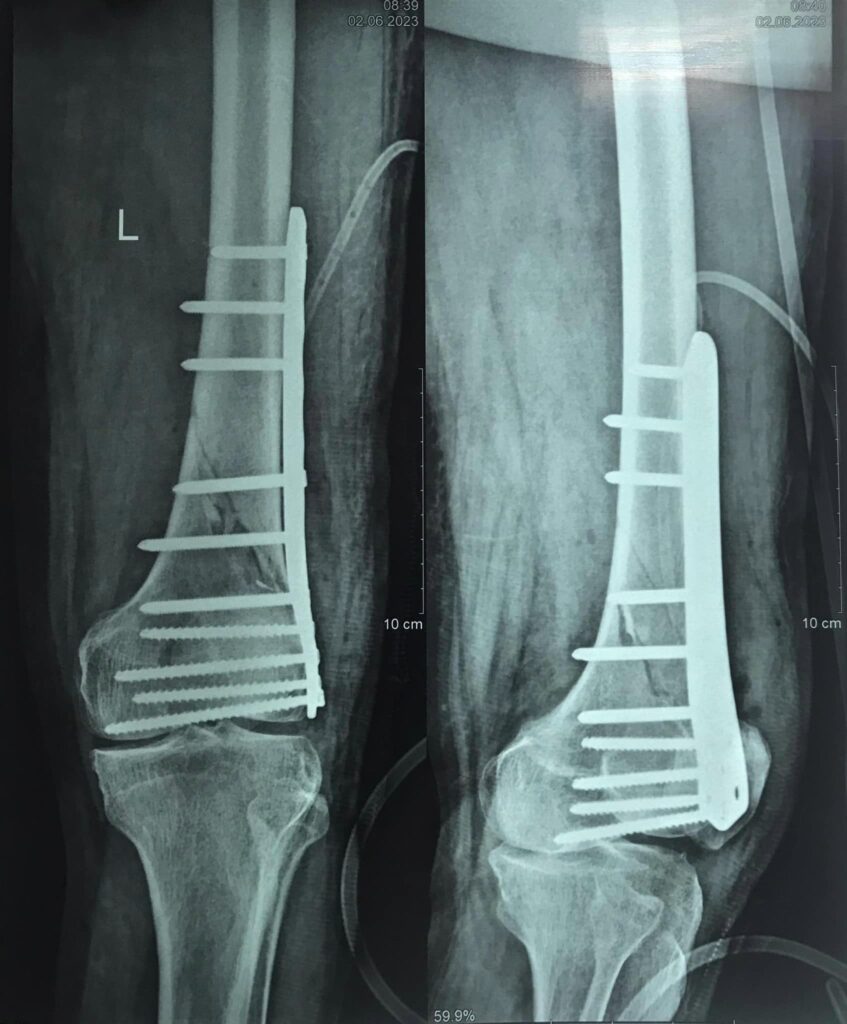

Kết quả sau phẫu thuật kết hợp xương trong gẫy đầu dưới xương đùi bằng nẹp khoá trên bệnh nhân cao tuổi loãng xương.

Gãy đầu dưới xương đùi là một gãy xương lớn, phức tạp, thường ảnh hưởng đến chức năng vận động của khớp gối. Nẹp khóa đầu dưới xương đùi giúp cố định vững chắc ổ gãy theo cấu trúc giải phẫu. Bệnh nhân hài lòng với kết quả điều trị.